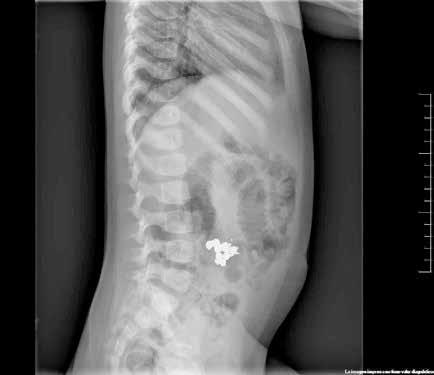

Figura 1. Radiografía de tórax en bipedestación AP y Lat.

Lesiones residuales/cicatriciales en campo superior izquierda, con aumento de densidad de parénquima, bronquictasias y pérdida de volumen, en relación con antecedente de TBC. Parénquima pulmonar derecho aceptablemente ventilado. Siluesta cardiovascular normal.